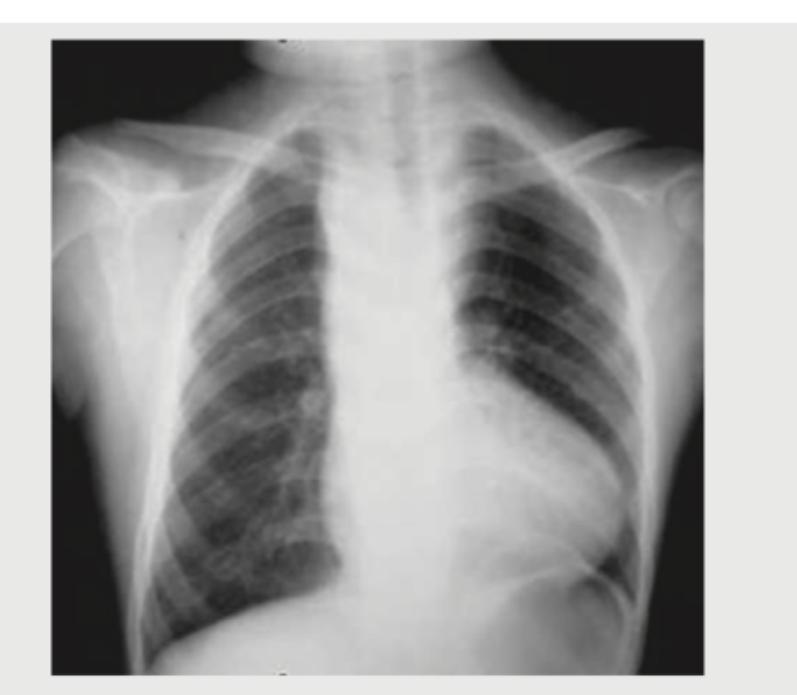

Identify the congenital heart disease presenting with cyanosis in CXR: (Recent NEET Pattern 2016-17)

Explanation: ***Tetralogy of Fallot*** - The chest X-ray shows a **boot-shaped heart** (coeur en sabot) due to right ventricular hypertrophy and a concave pulmonary artery segment, which is a classic finding in Tetralogy of Fallot. - This cyanotic congenital heart disease is characterized by four defects: a **ventricular septal defect**, **pulmonary stenosis**, **overriding aorta**, and **right ventricular hypertrophy**. *Truncus Arteriosus* - This cyanotic CHD involves a **single arterial trunk** arising from the heart supplying systemic, pulmonary, and coronary circulations. - CXR typically shows **cardiomegaly with increased pulmonary vascular markings** and a **right-sided aortic arch** in 30% of cases, not the boot-shaped heart seen here. - The pulmonary artery segment is **prominent or convex**, contrasting with the concave segment in Tetralogy of Fallot. *Ebstein anomaly* - This anomaly involves the **tricuspid valve** being displaced into the right ventricle, often leading to cardiomegaly and a **"box-shaped" or "globular" heart** on CXR, which is not depicted. - It can cause cyanosis, but the characteristic CXR finding is **massive cardiomegaly with diminished pulmonary vascular markings**, not a boot-shaped heart. *Snowman heart* - The "snowman heart" or **"figure of 8" sign** is characteristic of **total anomalous pulmonary venous return (TAPVR)**, specifically the supracardiac type. - This appearance is due to the dilated superior vena cava and the vertical vein draining into it, creating the "head" of the snowman, which is not seen in the provided image.